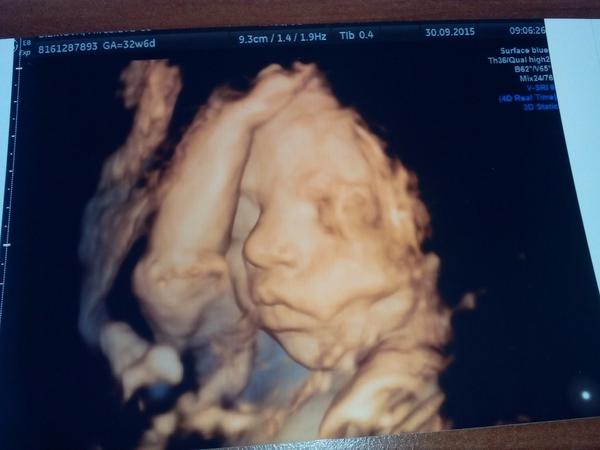

a inak este taky dotaz...nie vzdy sa babo ukaze hned tvariickou, to je jasne. Kamaratky co boli u ineho doktora chodili aj na 5x na 3d s tym ze...nevidno ho pridte o tyzden...nasa mala ani za toho otocit sa, normalne som bola nervozna za grochala, ze ty kokos isto ma naobjednavane zeny a tu sa s nami dve hodiny natahaju. A on ? Uplne pokojny, žiadne stresy, ziadne nahanacky...po dvoch hodinach na 4x sa podarilo ukazat tvaricku. Takze fakt je super 🙂